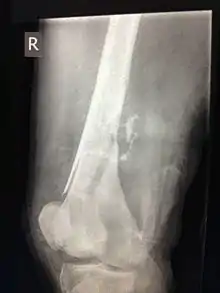

Вогнепальна рана (лат. vulnus sclopetarium) — пошкодження тканин і органів з порушенням цілості їх покрову (шкіри, слизової або серозної оболонки), викликане вогнепальним снарядом і характеризується зоною первинного некрозу і змінами, що обумовлюють утворення в навколишніх тканинах осередків вторинного некрозу, а також неминучим первинним мікробним забрудненням, що значно збільшує ризик розвитку ранової інфекції.

- пошкодженням кісток і суглобів;